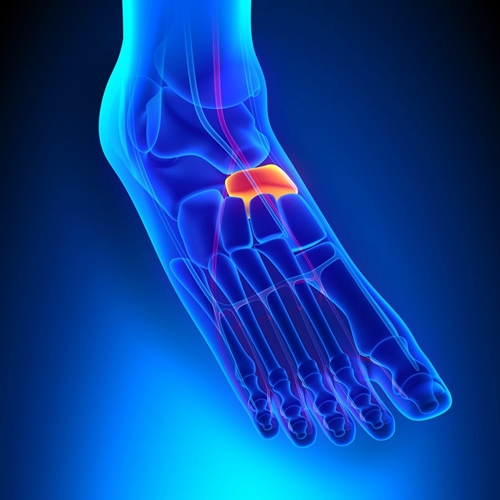

주상골(navicular bone)은 발목뼈(족근골)(tarsal bone)를 구성하는 뼈(bone) 중 하나입니다. 위치상으로 살펴봤을 때 입방골(cuboid bone)과 설상골(cuneiform bone), 그리고 거골(talus) 사이에 자리 잡은 뼈(bone)입니다. 그렇다 보니 방향적인 위치상 발목 안쪽(internal ankle)으로부터 타고 내려와, 실질적으로 발의 아치(foot arch)가 가장 높게 실리게 되는 위치상에 존재하게 됩니다. 주상골(navicular bone)의 자세한 모습과 위치는 사진을 통해서 제대로 살펴볼 수 있습니다.

사진에서 살펴본 것과 같이 주상골(navicular bone)은 단일한 뼈(bone)입니다. 하지만 부주상골증후군(accessory navicular syndrome)은 주상골(navicular bone)이 하나가 아닌 증상과도 같습니다. 그래서 그 이외의 뼈(bone)를 부주상골(accessory navicular bone)이라 부릅니다. 기본적으로 부주상골(accessory navicular bone)은 더 작은 크기(small size)로 형성되어있으며, 그 위치는 부주상골(accessory navicular bone)이라는 이름답게 주상골(navicular bone) 옆(lateral)에 자리 잡게 됩니다.

부상골(accessory navicular bone)이 존재할 때, 발목뼈(tarsal bone)들 사이에서는 하나의 관절(joint)이 더 형성됩니다. 이로 인해 불이익이 될 수 있는 부분도 존재하겠지만, 이익이 될 수 있는 부분도 분명 존재합니다. 앞서 이야기했던 사항들과 더불어 고려해볼 때, 주상골(navicular bone)들끼리의 더 많은 미끄러짐 관절운동(sliding joint movement)과 함께, 내측 종아치(medial longitudinal arch)를 유지(maintain)하거나지지(supporting)하는 측면에서 더 많은 조직들이 활성화(tissue activation)될 것입니다. (부상골(accessory navicular bone)로 인해, 이곳에서도 부착(attachment)되고 경유하게 되는 조직(tissue)들이 그만큼 존재하므로)